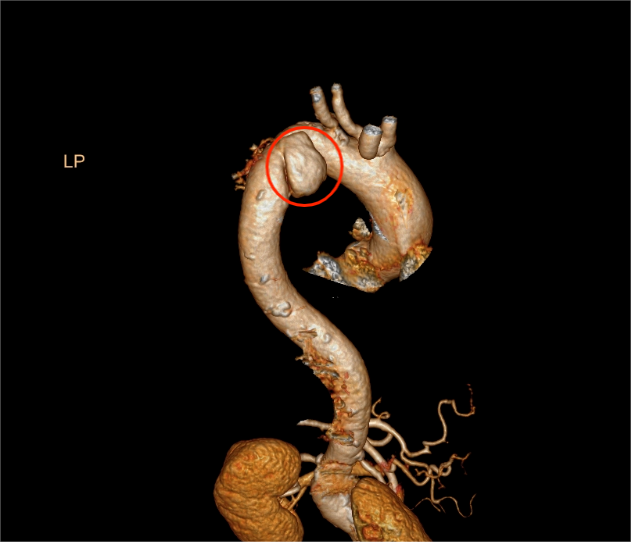

患者路女士,75岁,因车祸后出现胸部疼痛、呼吸困难,被紧急送至医院。检查发现其伤情复杂,包括多发肋骨骨折、锁骨骨折、颅骨及腰椎骨折、脑脊液漏、创伤性血气胸、应激性溃疡伴出血、创伤性休克等,后续进一步诊断为创伤性主动脉夹层(B型)。面对如此涉及多个系统、部位的重症伤情,医院立即启动多学科协作机制。

泛血管疾病管理中心在此过程中发挥了重要的协调与整合功能。中心秉承“全身血管一体考量”的理念,统筹心胸外科、心内科、神经外科、骨科、麻醉科、重症医学科等相关专科资源,为患者制定个性化、系统化的治疗方案。在控制血压、稳定生命体征的基础上,医疗团队先后为患者实施“冠状动脉造影术”、“主动脉覆膜支架腔内隔绝术”及“肋骨骨折切开复位内固定术”。术后,患者经重症监护与心胸外科病房的协同康复,病情逐步平稳,最终好转出院。